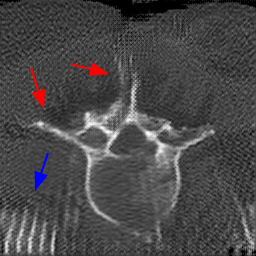

Disentanglement and explicit shape constraints. As shown in Fig. 4, we can see streak metal artifacts nearly everywhere in . M1 can roughly disentangle artifacts and anatomical information but strong vertical artifacts and strange air area appear in (see red arrows of M1 in Fig. 4). For the anatomical structure, M1 learns to segment vertebrae with fully supervised and applied on various CT images, but fails to suppress the false bony structure in and as may misclassify some metal artifacts as bone.

Implicit shape constraints. With , all segmentations are improved with higher Dices and smaller ASDs, see Table 1. As shown in Fig. 4, , and become similar but the high density bone is not correctly segmented in as it maybe treated as metal artifacts. Comparing between M2 and M1, the abnormal air region disappears but metal artifact reduction performance is still not satisfactory.

Anatomy-aware generation. With AADE layer in M3, , and are substantially improved as shown in Table 1. Note, is used as attention map, so we do not expect it to be identical to . In , metal artifacts are further suppressed comparing with M2. Thus, AADE is critical to our anatomy-aware artifact disentanglement framework. With the special structure, can be punished in the image translation and reconstruction processes and the other encoders and generators receive more guidance. However, as shown by blue arrows in Fig. 4, we observe a shadow of vertebra edge of appears in of M3 and the vertebra boundaries get smoothed out in . It may be because sharp edges are encoded as metal artifacts and forced to be added to by artifact consistency loss .

Removal of . To mitigate vertebrae shadows, we remove . The segmentation performance of most images in M4 gets improved because of better synthetic images. Overall, in M4 yields the best segmentation performance for CBCT images with an average Dice of 0.847 and an average ASD of 1.54 mm. For the synthetic images, M4 generates with the best quality and least metal artifacts among all the models. M4 also outputs without vertebra shadows. The results indicate our shape-aware network could preserve anatomical details and transfer the metal artifacts precisely without .